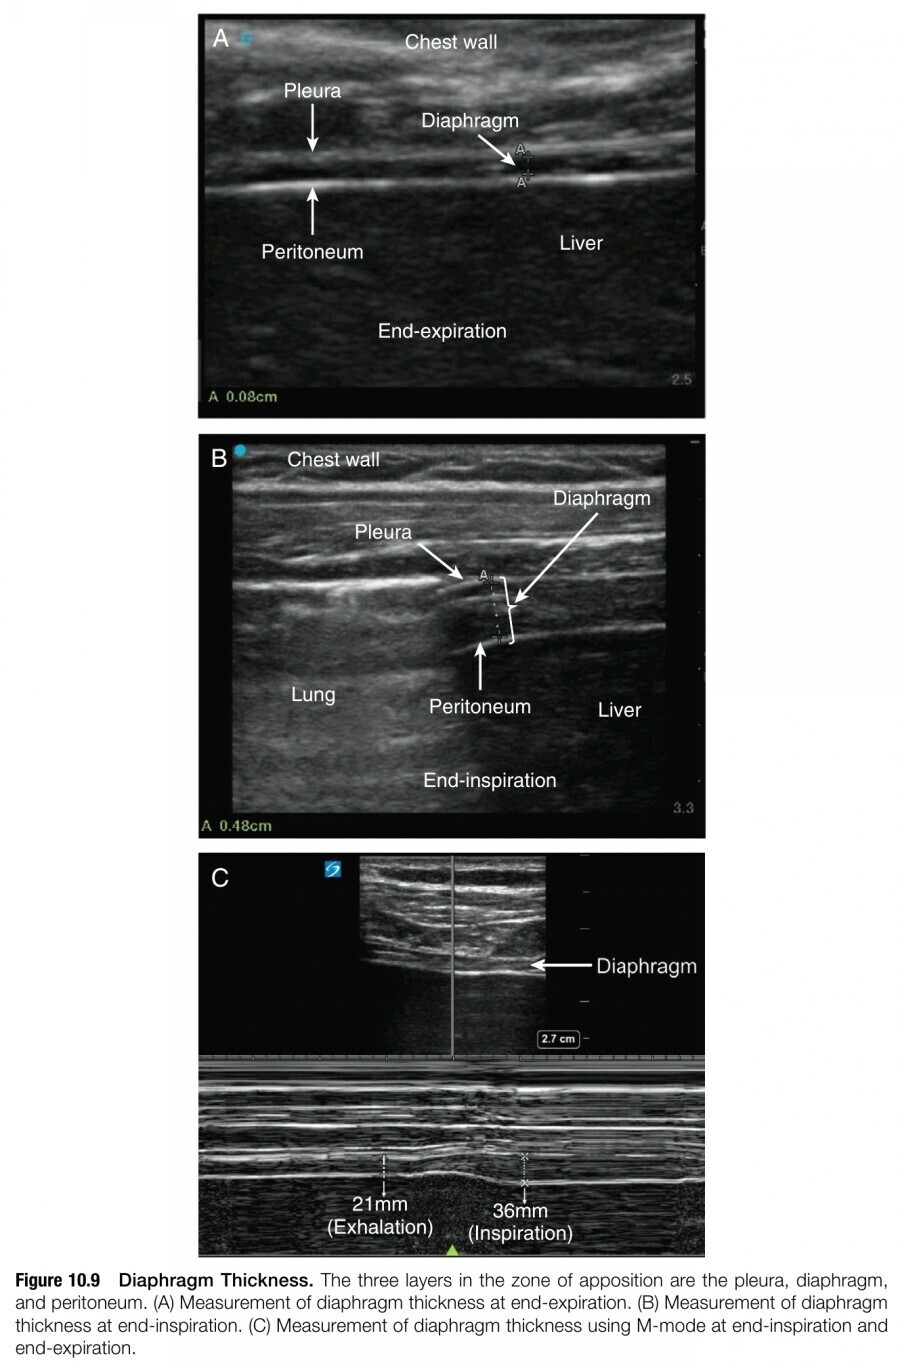

2. Diaphragmatic function을 측정하는 두 번째 technique은 diaphragm thickness의 측정이 있다. Diaphrgam이 ribs와 만나는, zone of apposition이라고 불리는 midaxillary line에 higher-frequency linear transducer(6~13 MHz)를 위치한다(figure 10.8). High-frequency linear transducer로 보면, diaphragm은 3개의 distinct layer로 이루어진 thin hyperechoic strip으로 보인다; Muscle의 isoechoic layer가 2개(pleura, peritoneum)의 hyperechoic layer 사이에 샌드위치처럼 껴있다. Diaphragm thickness는 two-dimensional mode나 M-mode를 이용해서 측정한다(figure 10.9). 건강한 사람 대부분에서 thickness는 end-expiration 시 1.8mm에서 3mm 사이로 다양하다.